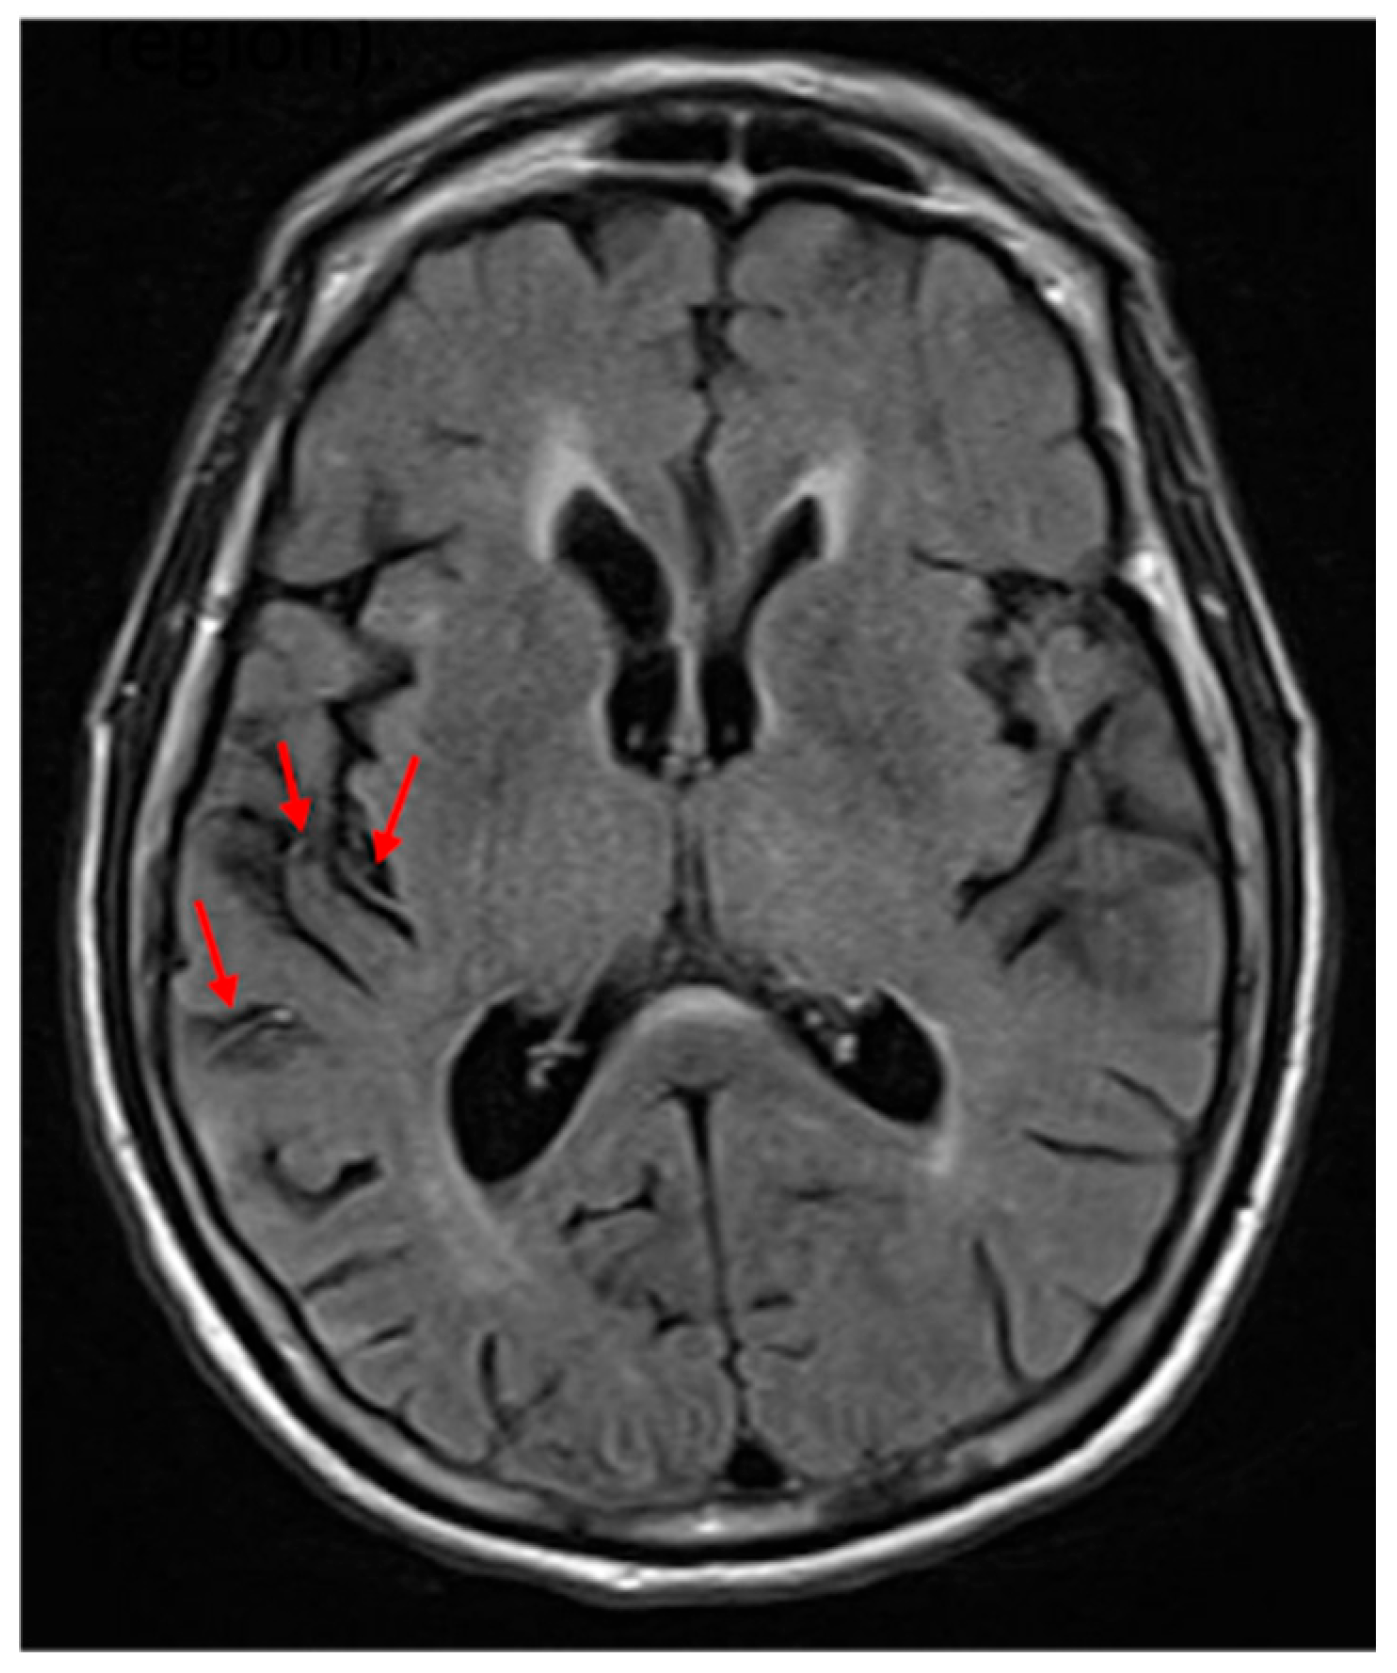

One limitation in studying individuals with acute stroke is that areas of hypoperfusion beyond the infarct may be responsible for acute deficits [17,18]. Studies using perfusion imaging have shown that in acute stroke, hypoperfusion beyond the infarct contributes to deficits, including neglect [17,19,20]. Studies have also shown that reperfusion of dorsal regions results in improvement of VCN, and reperfusion of ventral regions results in recovery of SCN [21]. However, perfusion imaging is not always available. In its absence, previous work has shown that FLAIR hyperintense vessel (FHV) number and site can be used to estimate the volume [22,23] and site [24] of hypoperfusion. An FHV (see Figure 1) indicates slow blood flow in that area, and the total number can be used to estimate the volume of hypoperfusion [22]. Furthermore, the site of the FVH is strongly associated with the site of significant hypoperfusion [24].

On FLAIR sequences, we identified FHVs in 4 MCA regions, according to a published method [22]: frontal, temporal, parietal, and insular, as well as ACA and PCA territories (Figure 1). Each region was scored from 0 to 2: 0 = no FHVs; 1 = 1–2 FHVs on 1–2 slices; 2 = 3 or more vessels on 1 slice; or 3 or more slices with at least 1 FHV (total = 0–12). The stroke core was automatically delineated with ADS (https://www.nitrc.org/projects/ads, accessed on, https://www.nature.com/articles/s43856-021-00062-8, accessed on 1 December 2024) and revised by an experienced neuroradiologist (AVF). The vascular territories affected were defined according to the digital atlas of arterial territories (https://www.nitrc.org/projects/arterialatlas, accessed on 1 December 2024, https://www.nature.com/articles/s41597-022-01923-0, accessed on 1 December 2024). Total infarct volume and lesion load in the right and left anterior cerebral artery, middle cerebral artery—frontal, middle cerebral artery—parietal, middle cerebral artery—temporal, middle cerebral artery—occipital, posterior cerebral artery—temporal, and posterior cerebral artery—occipital were calculated using the pipeline that utilized b0, Diffusion Weighted Imaging (DWI), Apparent Diffusion Coefficient (ADC), and Fluid Attenuated Inversion Recovery (FLAIR) sequences.

Figure 1. FLAIR hyperintense vessels (two in the middle cerebral artery frontal region and one in the insular region). The red arrows point to the FLAIR hyperintense vessels.